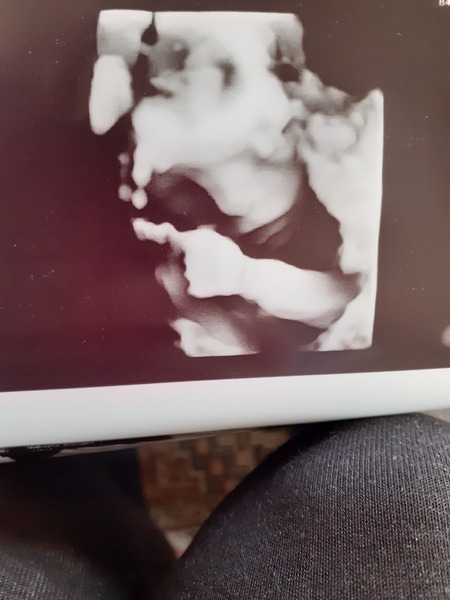

MOGMOGMOG85 · 23/07/2020 16:42

I hope no-one minds me sharing this here. Visibility with my fibroids was pretty crappy but he used 3D and we got a little glimpse of the face coming out of the void for just a split second - it was magical

@MOGMOGMOG85 Aaah congrats!! Welcome to the Boys club! Great scan pic. Does your hospital automatically do 3D?? I have a private scan booked Sunday so my DH can finally come. Looking forward to seeing something that isn't a grainy black and white 2D image 😂

@MOGMOGMOG85 thats a beautiful scan pic! Glad your scan went well to and little one was performing, Congrats on having a boy. Errol is a sweet name, and not too popular either (not that I'd let popularity put me off a name).